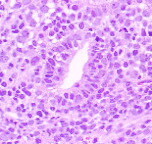

HE染色による組織標本では内膜の上皮が少量認められ核の腫大が認められるものの明らかな増生は示しておりません。主に間質部分の増生からなっており、個々の細胞のN/Cは高く小型核小体が認められます。

少数の多核細胞や大型細胞を認め、また核分裂像も散見されます。脈管への浸潤もあり悪性と考えらるが特徴の乏しい像でoriginの同定が困難な像です。内膜間質腫瘍の他未分化癌、脂肪肉腫や血管系腫瘍との鑑別診断が必要とされました。そこでorigin同定のため免疫染色を実施致しました。